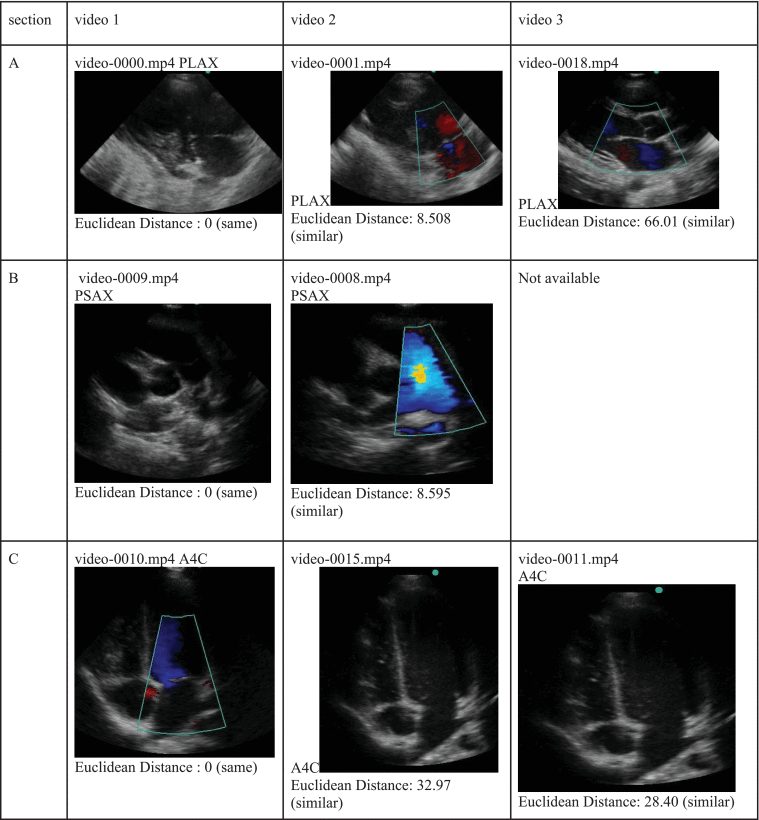

Unsupervised Discovery of Echocardiographic Views for Rheumatic Heart Disease Diagnosis

IST-Africa 2023

Health

Towards AI Based Diagnosis of Rheumatic Heart Disease: Data Annotation and View Classification

IST-Africa Conference (IST-Africa) 2022